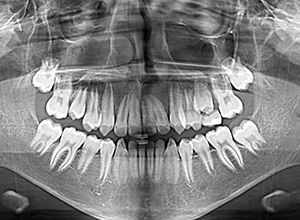

| パノラマ所見 | 上顎左右側犬歯は近心傾斜し側切歯歯根に重なるように認められた。 |